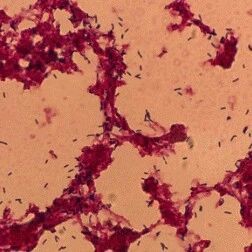

一例李斯特菌性脑膜炎合并脓毒血症的救治分析